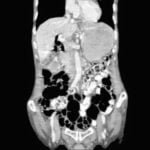

Clinical scenario : A 77-year-old female presented to our hospital with a history of lower GI bleed and colonoscopic examination showed multiple lesions in sigmoid colon and in transverse colon . Fig 1 and Fig 2 What is the diagnosis? Fig.1 Multiple lesions seen on colonoscopy   Fig2 Multiple lesions seen   Click here to […]